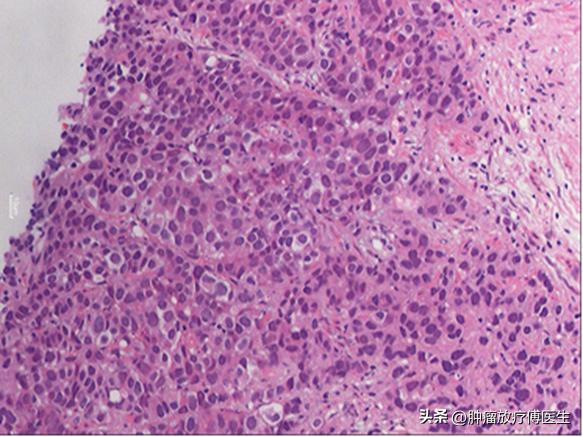

患者,男,68岁。于2013年11月出现排尿困难,伴尿流变细、尿频、尿急,夜尿次数增多,4~5次/晚。2014年2月因排尿困难进行性加重就诊我院泌尿外科,查PSA 11.27ng/ml,行盆腔MRI示前列腺大小约4.0cm×3.2cm×3.3cm,内外腺界限不清,信号不均匀,内可见结节样信号影,侵犯包膜。双侧盆壁可见淋巴结影,较大的范围约为1.8cm×1.5cm,DWI高信号,增强后可见环形强化。考虑前列腺癌,伴双侧盆腔淋巴结转移可能性大。全身骨扫描未见异常。2014年2月27日行前列腺穿刺活检病理提示(图1):左侧前列腺组织穿刺活检标本:低分化前列腺腺泡细胞癌,Gleason积分5+4=9;右侧前列腺组织穿刺活检标本:前列腺腺泡细胞癌,Gleason积分3+5=8。

图1 2014-2-26 前列腺穿刺活检病理